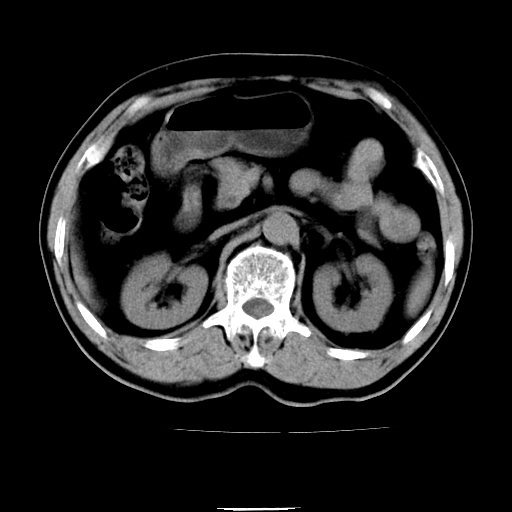

以下是引用chenqiong在2010-3-25 20:56:00的发言:[br]1、胆囊炎,胆囊息肉[br]2、肝内胆管及胆总管扩张,胆总管下端结石[br]3、十二指肠乳头旁憩室

以下是引用zxl51642在2010-3-26 10:47:00的发言:[br]胆囊炎,胆囊息肉,胆总管扩张,但未看到明显肿块,肝内胆管扩张不像恶性,炎性狭窄或阴性结石可能吧,建议mrcp,右肾小囊肿